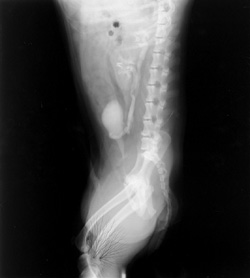

Click to enlarge Click to enlarge

Static

Static causes black branching artifact on the film due to exposure of the film to the elecrical spark of the static discharge.